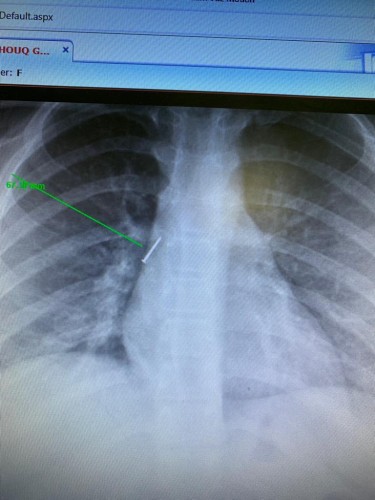

نجح –  بفضل الله – فريق طبي بمستشفى الأمير متعب بن عبدالعزيز بسكاكا ممثلاً بقسم جراحة الصدر، بإنقاذ طفلة في حالة نادرة وصلت لقسم الطوارئ بالمستشفى.

وكانت الطفلة 11 عاماً قامت وعن طريق الخطأ استنشاق دبوس ليستقر في القصبة الهوائية اليمنى داخل رئة الطفلة, وقد استقبلت إحالة الطفلة من أحد مستشفيات المنطقة إلى مستشفى الامير متعب بن عبدالعزيز، ليتمكن الفريق الطبي وبعد القيام بالفحوصات المخبرية والإشعاعية اللازمة من إجراء العملية وذلك باستخدام المنظار القصبي وبشكل دقيق من استخراج الجسم الغريب وحالتها مستقرة.